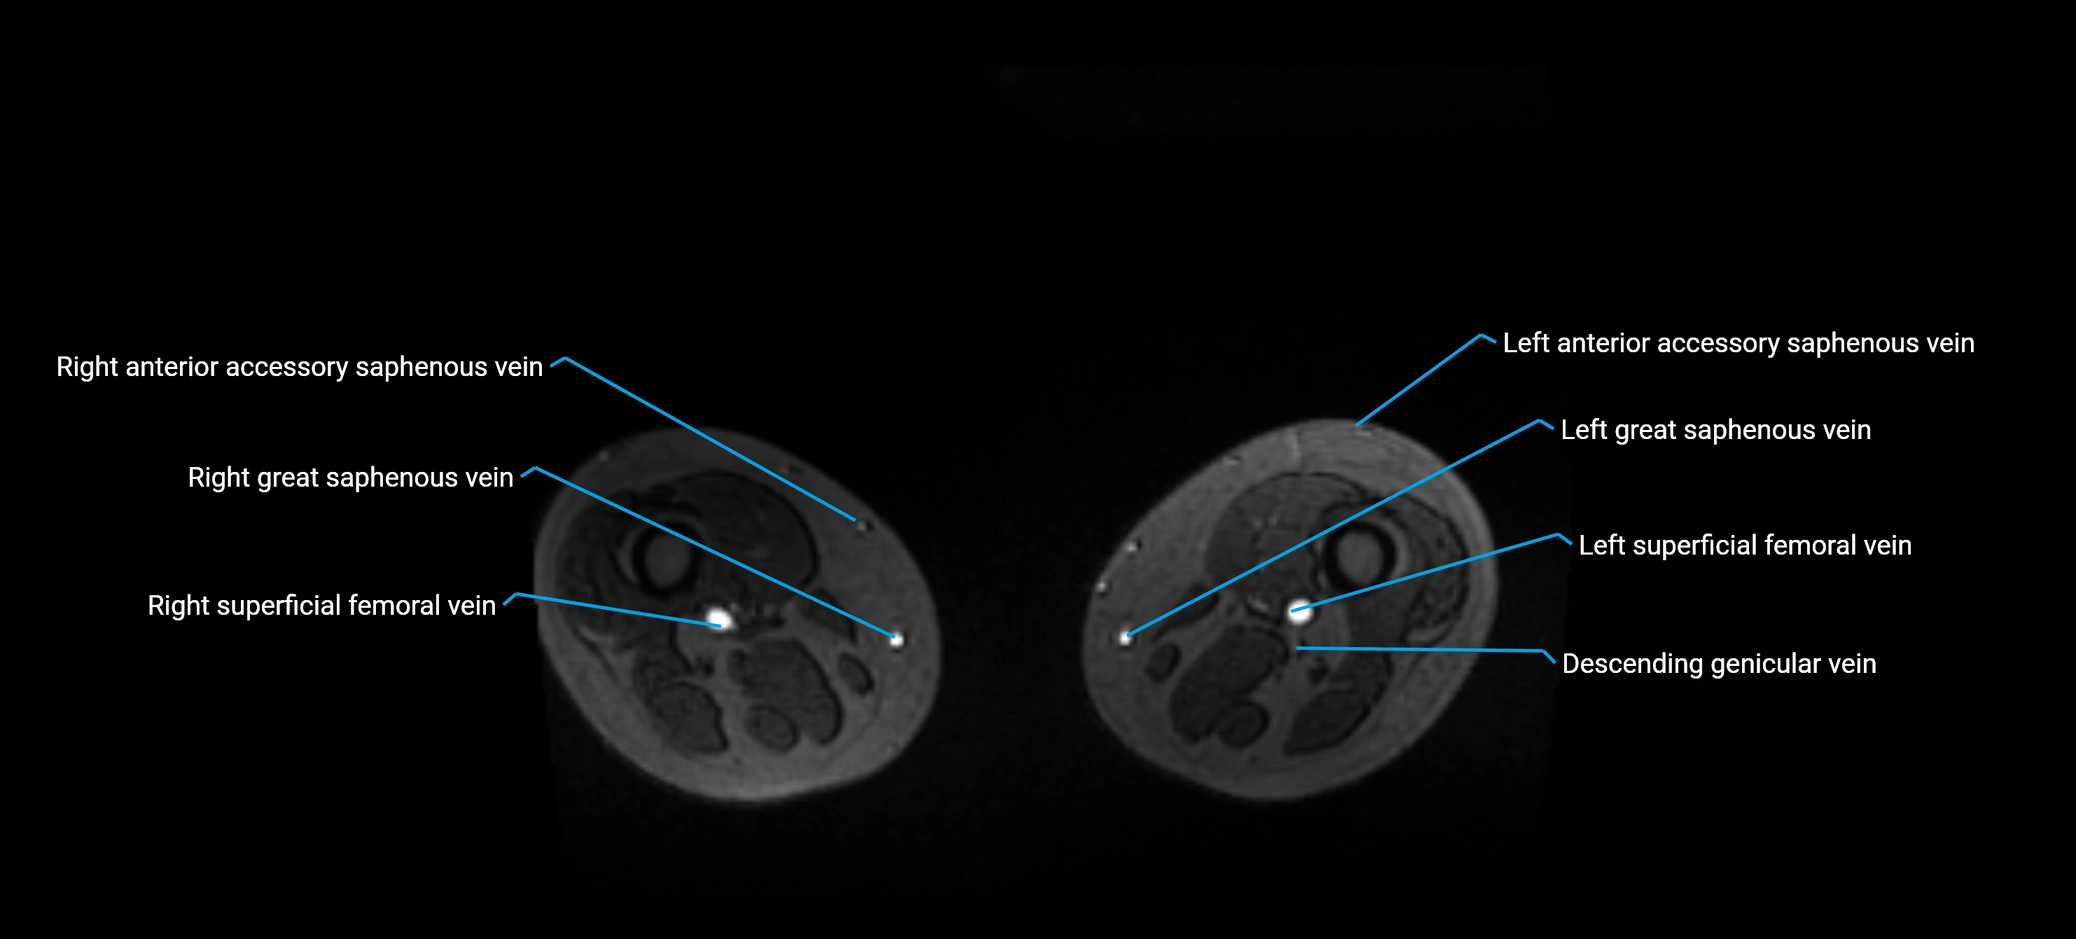

MRI image

image